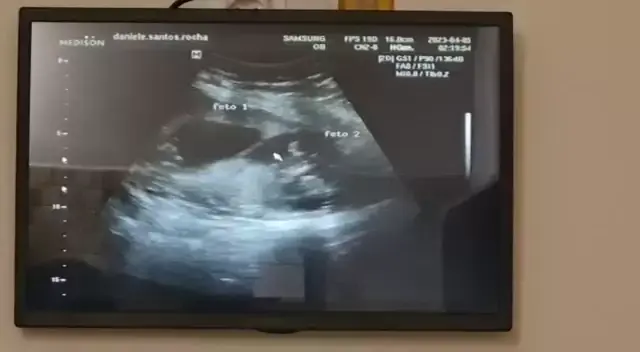

Dani Santos

outra ultrassom pra ver os gêmeos 13 semanas 😍😍😍😍